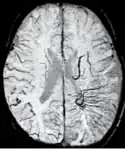

Multiple sclerosis (MS) is usually studied with FLAIR and contrast enhanced T1 imaging. SWI adds to this by revealing the venous connectivity in some lesions and presents evidence of iron in some lesions. This key new information may help understand the physiology of MS.[4]

The magnetic resonance frequency measured with an SWI scan was shown to be sensitive to MS lesion formation. The frequency increases months before a new lesion appears on a contrast enhanced scan. At the time of contrast enhancement the frequency increases rapidly and remains elevated for at least six months.[5][6]